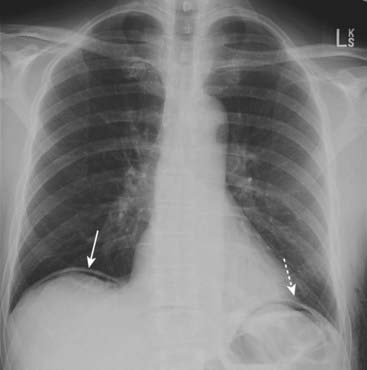

Figure 15-1 Free air beneath the diaphragm.

There are thin crescents of air beneath both the right (solid white arrow) and left (dotted white arrow) hemidiaphragms representing free intraperitoneal air. The patient had undergone abdominal surgery 3 days earlier. Free air can remain for up to 7 days after surgery in an adult, but serial studies should demonstrate a progressively decreasing amount of air.